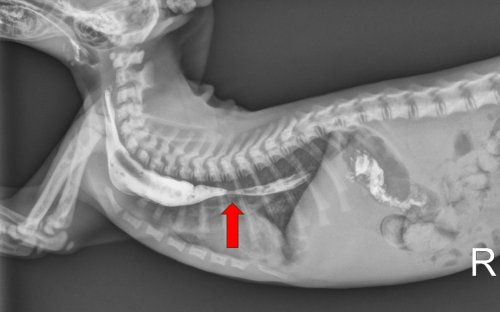

Imaging revealed the kitten’s esophagus was under 1 mm in diameter compared with 8 mm expected at his age.

There, radiographs revealed a stricture in Ginger’s esophagus. Subsequent CT scans showed that his esophagus was opening less than 1 mm, far below the 8-mm opening typical for a healthy 6-week-old kitten. CT findings also included pneumonia, likely due to aspiration from regurgitation.1